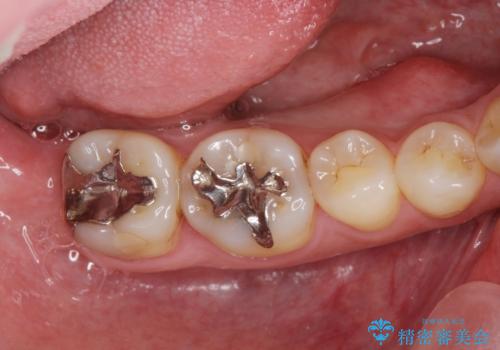

[セラミック治療] 銀歯だらけの歯を白く

- 銀歯だらけで見た目の気になる歯を白くしたい。と希望され来院されました。

銀歯の下には虫歯の再発や歯石の沈着、さまざまの問題が散見されましたが一つづつ丁寧に問題を解決し、

長期的な予後の見込める治療を行っていきます。

ただ白いセラミックを装着するのではなく、虫歯をきっちりと取り切り精度の高いクラウンを製作することで再度の虫歯の発生確率を抑えることができます。